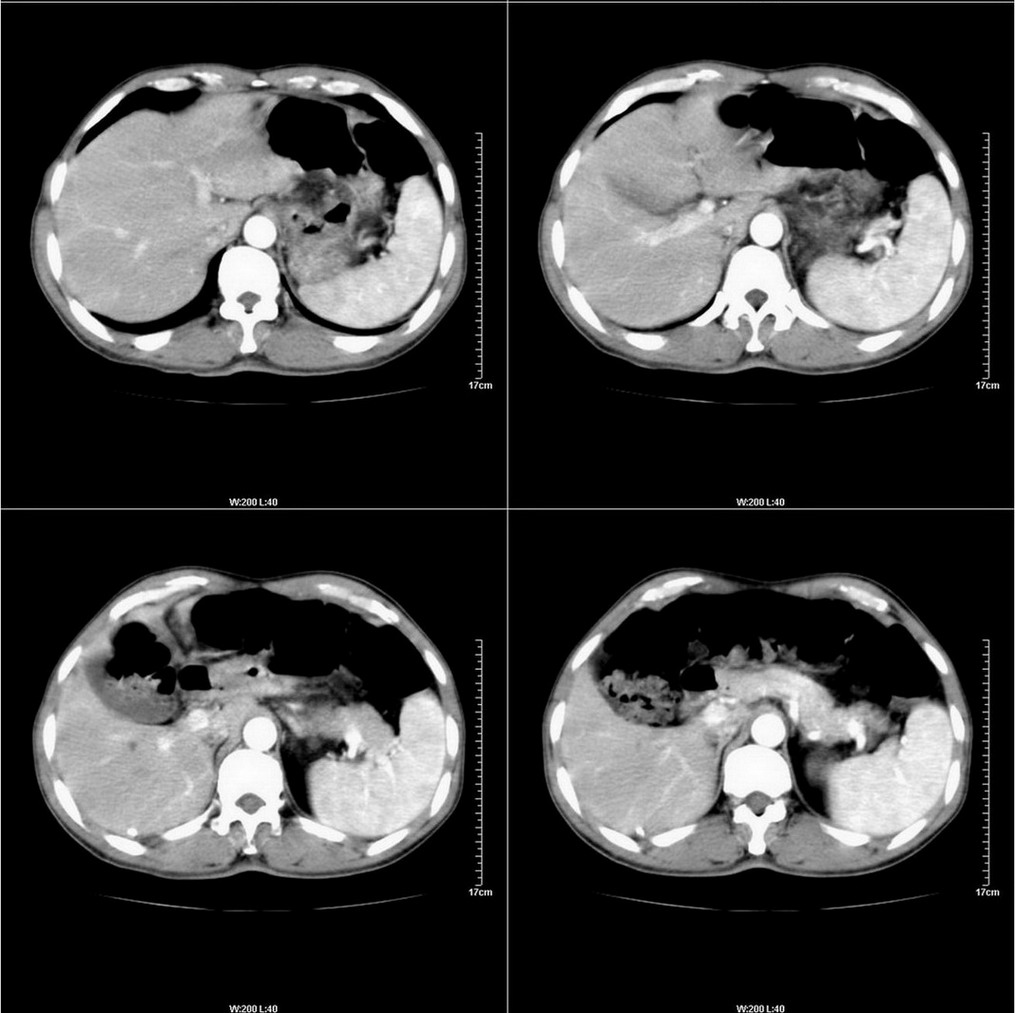

标题: CT14220:男性,59岁。腹部疼痛不适半年余。 [打印本页]

标题: CT14220:男性,59岁。腹部疼痛不适半年余。

胃壁弥漫增后,考虑胃炎溃疡

建议结合胃镜或钡餐检查,考虑胃底贲门癌可能性大。

肝实质未见明显异常;查查胃。

考虑:1、肝右叶下部小囊肿;

2、胃可能为准备充盈不良所致,必要时请胃镜进一步检查。